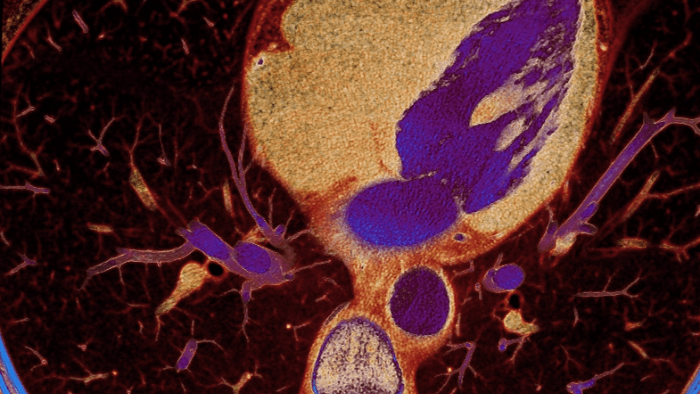

How spectral detector works

Spectral detector simultaneously absorbs and differentiates high and low energy from a single polyenergetic X-ray beam. Spectral results are acquired within a single scan without the need for special modes.

How Spectral CT technology works

Detector-based spectral CT simultaneously absorbs high and low energies in the same time and space.